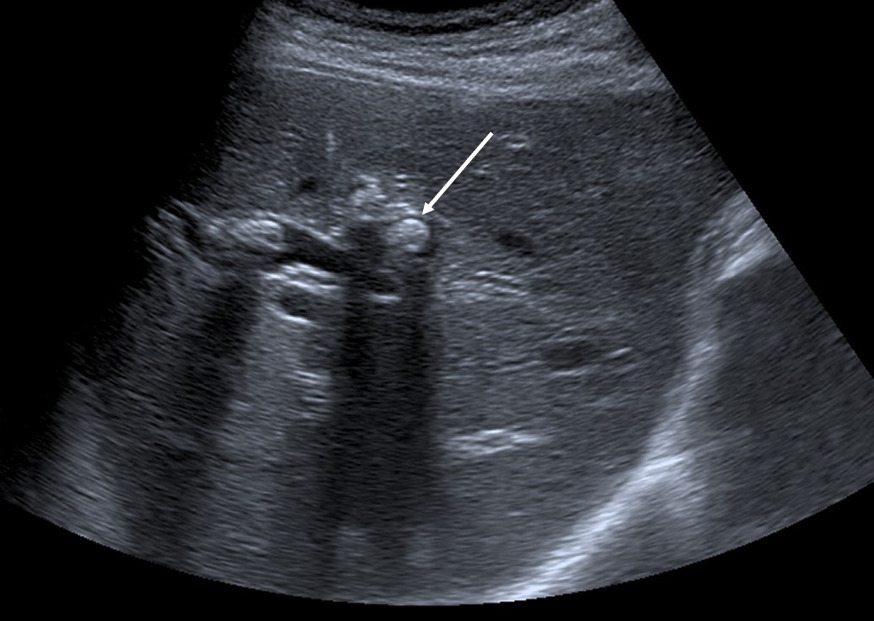

L’échographie hépatique est l’examen clé pour le diagnostic de syndrome LPAC. Celle-ci met typiquement en évidence les signes d’une microlithiase intrahépatique sous la forme d’images en « queue de comète » (échos de répétition liés à la vibration des microcristaux sous le faisceau d’ultrasons), de micro-­spots ou de « boue biliaire » (sludge) le long des canaux intrahépatiques (fig. 1A). Ces signes sont parfois difficilement identifiables, notamment en situation non sensibilisée et pour un opérateur non entraîné. Le principal diagnostic différentiel est représenté par les microhamartomes (ou complexes de von Meyenburg) qui peuvent parfois se présenter sous la forme d’artéfacts en queue de comète.9 Une échographie normale standard n’élimine pas le diag­nostic et il peut être nécessaire de répéter l’examen par un radiologue expérimenté et formé à la sémio­logie du syndrome LPAC. Moins fréquemment (5 à 10 % des cas), le syndrome LPAC peut se présenter sous la forme de vrais calculs (macrolithiases) intra- ou extrahépatiques (fig. 1B).4 Une lithiase vésiculaire n’est observée que chez un tiers des patients atteints de syndrome LPAC.

La cholangiographie par IRM est typiquement normale dans les formes habituelles, microlithiasiques, du syndrome LPAC. Elle n’est donc pas nécessaire au diagnostic dans la très grande majorité des situations. Elle doit être réalisée en cas de calculs intrahépatiques ou de dilatation des canaux biliaires en échographie afin d’évaluer le retentissement de ces calculs sur les voies biliaires et le parenchyme hépatique. Les calculs biliaires ne sont pas toujours visibles à l’imagerie par résonance magnétique (IRM), notamment quand leur taille est inférieure à 5 mm. Lorsqu’ils sont visibles, ils sont le plus souvent visualisés en hyposignal T1 et T2 sous forme de lacunes endobiliaires (fig. 2 A et 2B). Dans une série récente portant sur 125 patients suivis dans un centre expert et ayant tous eu une bili-IRM, 49 % présentaient des anomalies des canaux biliaires, parmi lesquelles 93 % de calculs intra­hépatiques et 38 % de dilatation des canaux biliaires.10 Ces anomalies morphologiques étaient plus fréquemment observées chez les porteurs d’un variant pathogène du gène ABCB4.